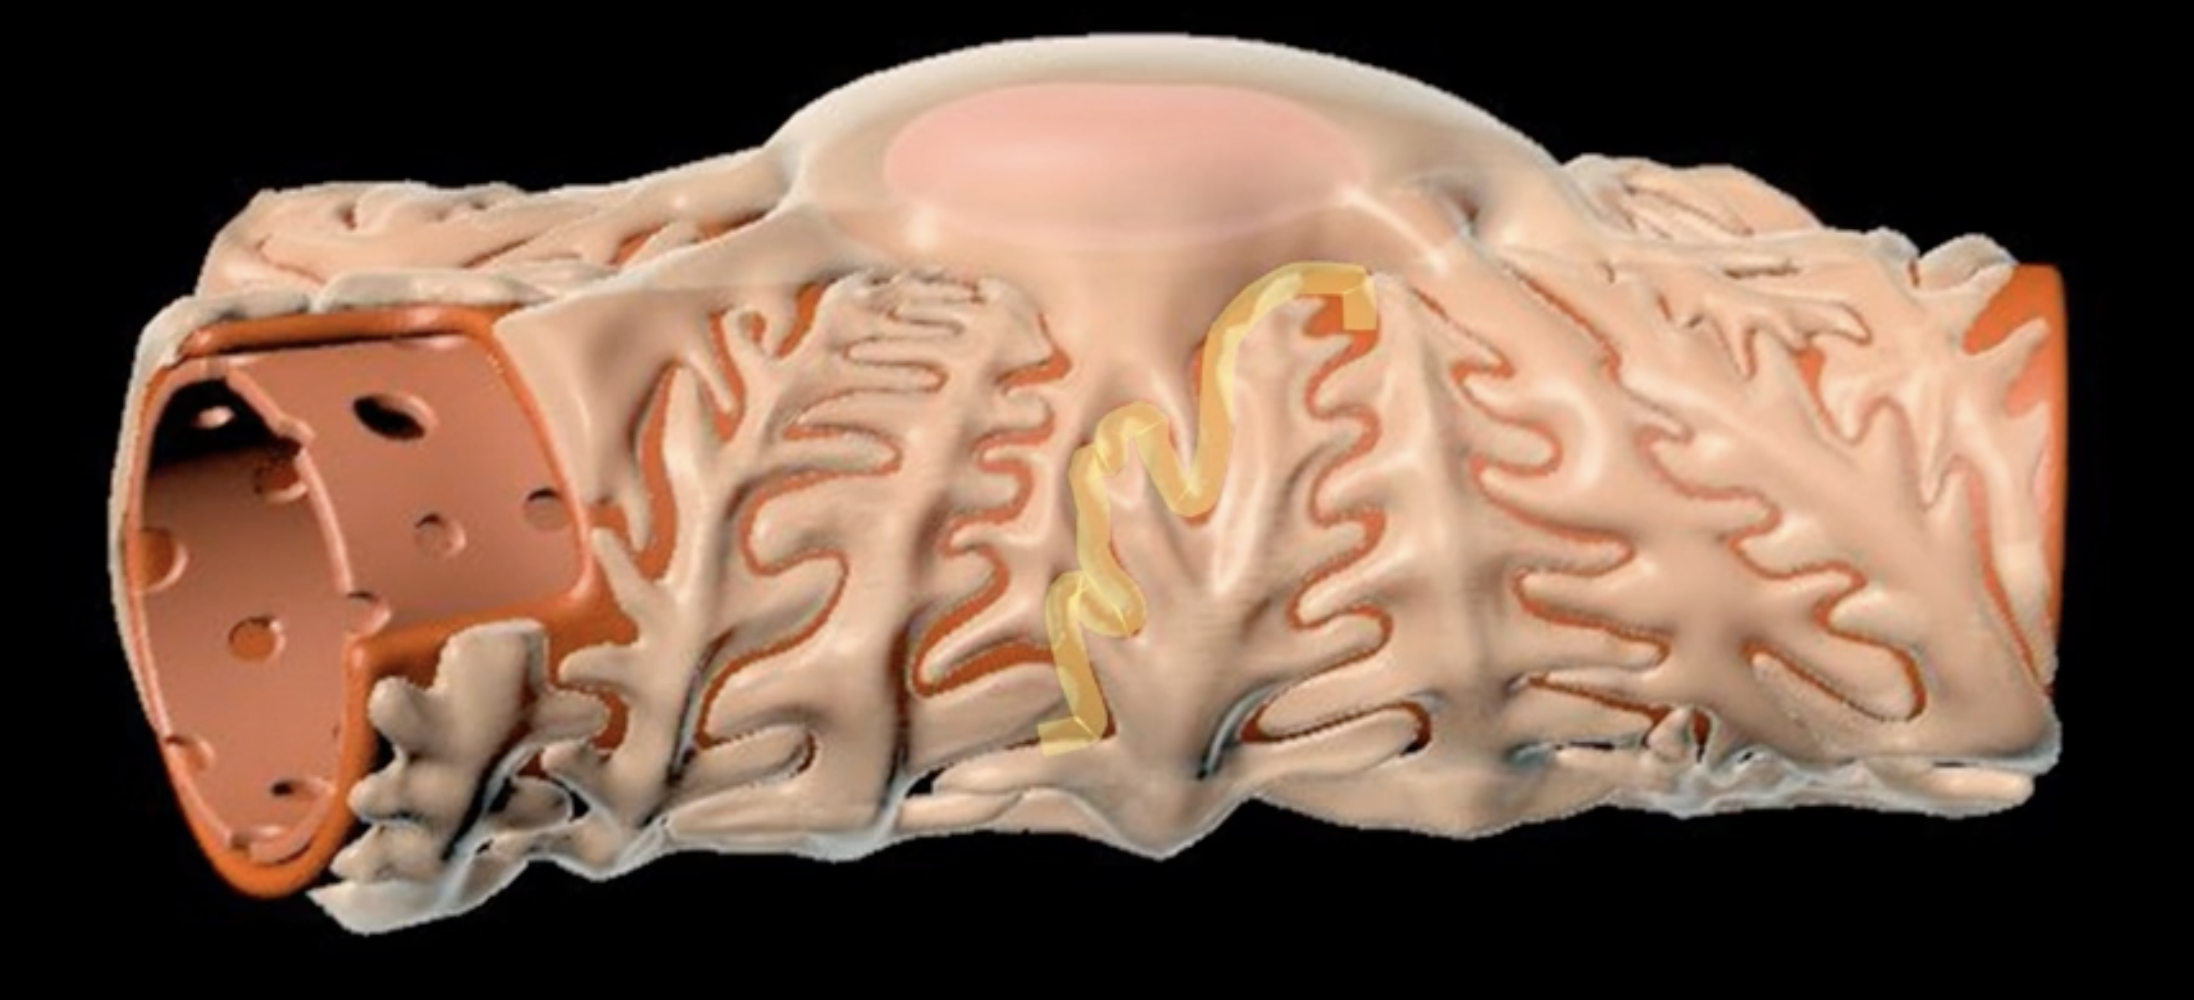

loop of Henle

red: descending limb

blue: ascending limb

red:

blue:

reabsorb ions

blue’s function

reabsorb water

red’s function

green: thick segment lined with simple cuboidal

purple: thin segment lined with simple squamous

green:

purple: